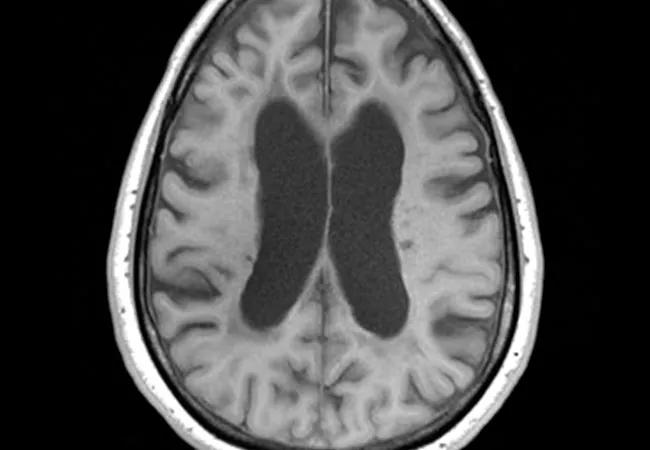

While relapsing-remitting MS generally involves focal inflammatory lesions, demyelination and periodic clinical relapses, progressive MS is characterized by more diffuse mechanisms, involvement of normal-appearing white and gray matter, and more prominent neurodegeneration affecting long-term brain function. The physiological processes elucidated by recent research in progressive MS provide important new targets for potential therapies.

Standard MRI has limited utility for assessing progressive MS: Unlike in relapsing-remitting MS, visible lesion activity is uncommon and does not correlate with disability. MRI markers have been enormously helpful in assessing treatment effectiveness in clinical trials for relapsing-remitting MS, but tools of this type are lacking for progressive disease.

• Brain volume measures, reflecting the greater severity of whole-brain atrophy in progressive MS relative to relapsing-remitting disease